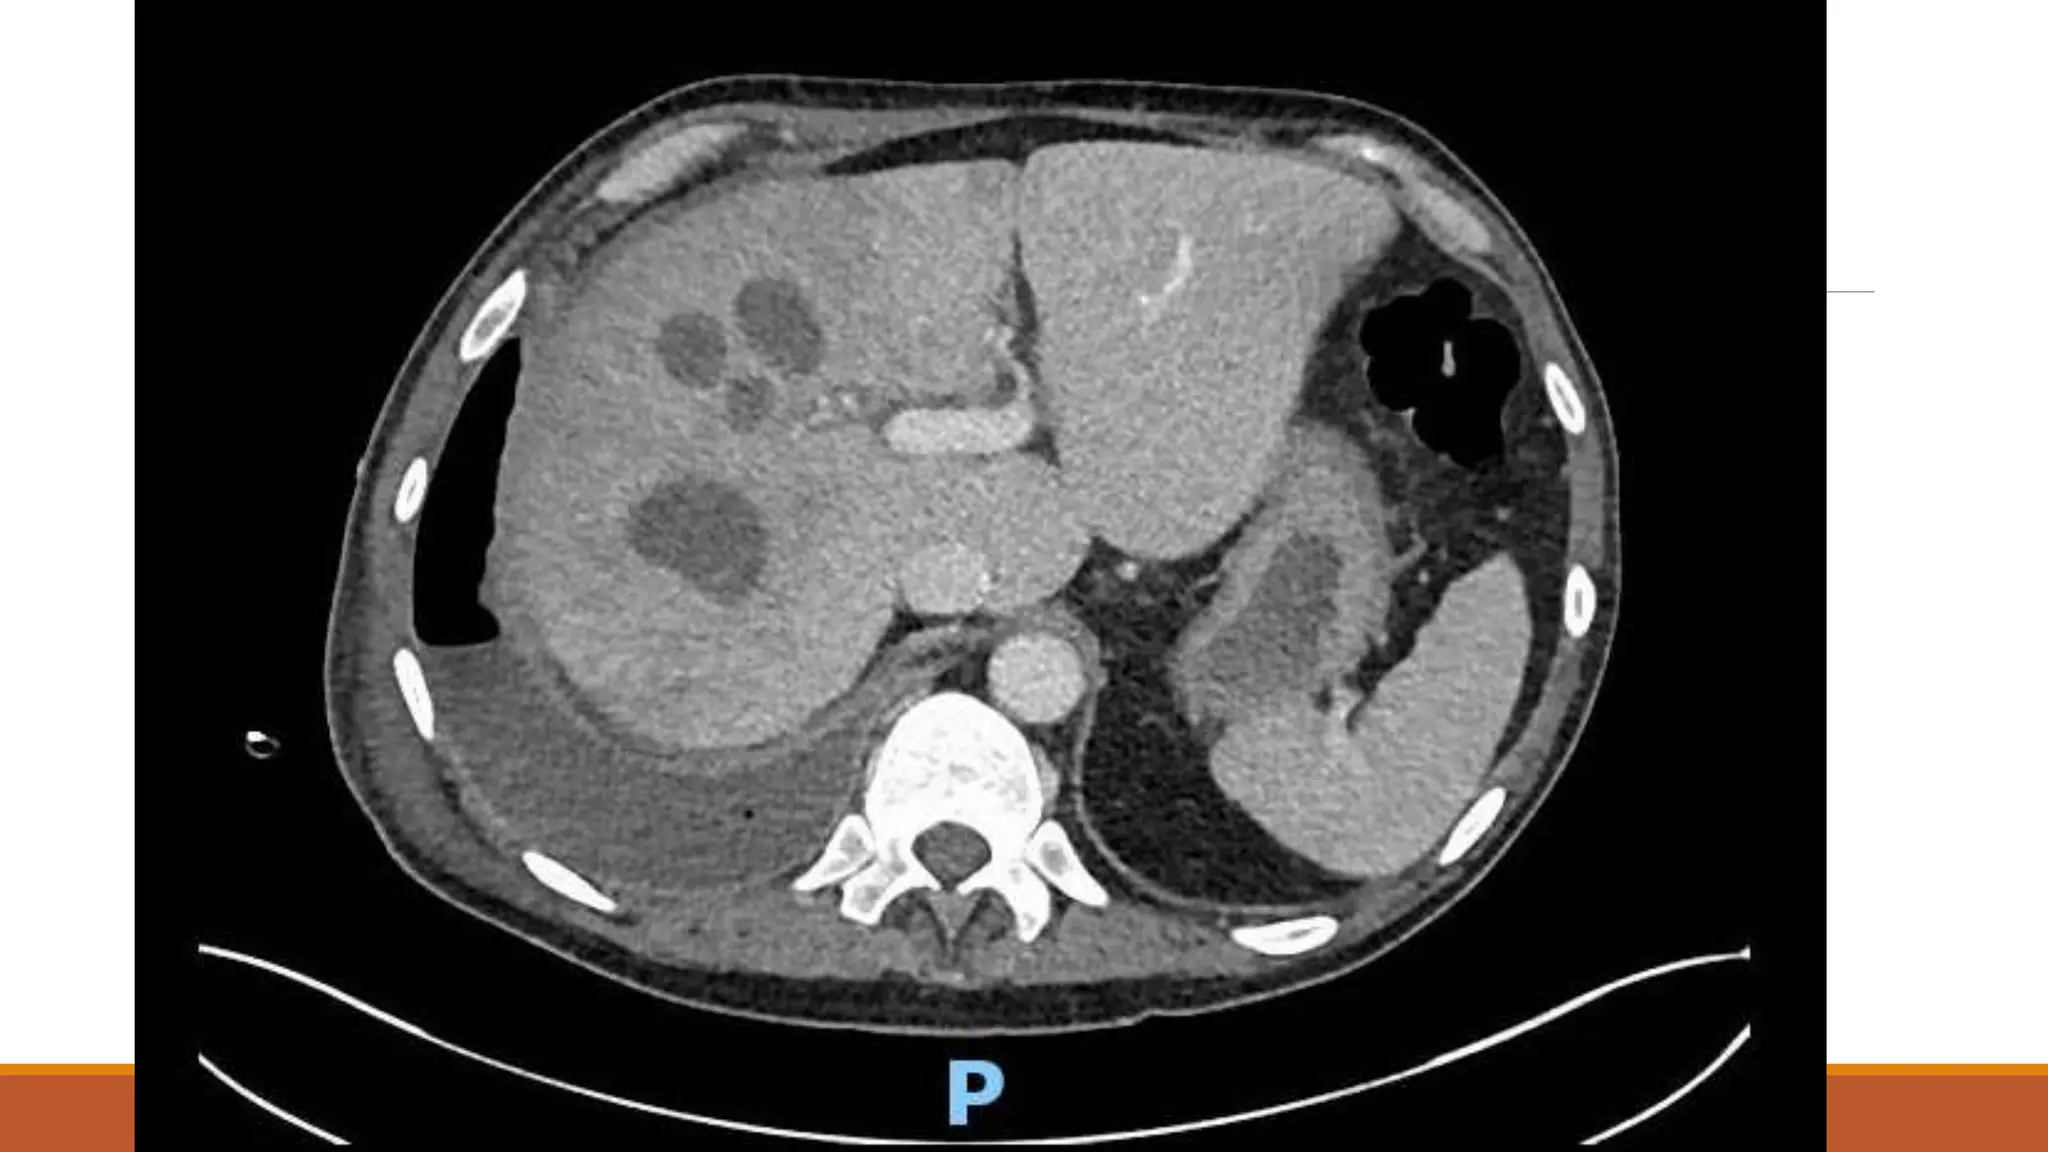

63 male

Normally F&W, no regular medications

Became unwell 7th Dec 2020 – cough, yellow sputum

Saw GP 23rd Dec – oral doxy

No real improvement – Clarithromycin 6/1/21

Again no improvement

Progressive loss of appetite and weight over a couple of months – given fortisip, which stopped

weight loss, but poor appetite continued

Progressive right shoulder pain and inability to lie on left side due to dyspnoea

On examination

OE: Acutely distressed, in significant pain and sats dropped to 80% when sat forwards, but 98%

when reclined at 60 degrees

Chest – no air entry right side